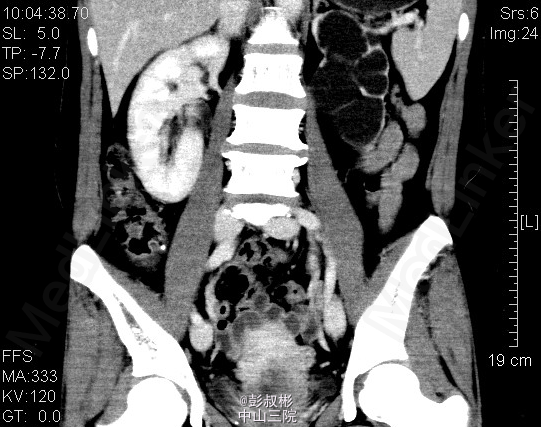

患者女性,47岁,左腹部胀痛1月余。既往有“双肾结石”病史10余年。其余见双肾CTU。根据检查判断肾的病变?